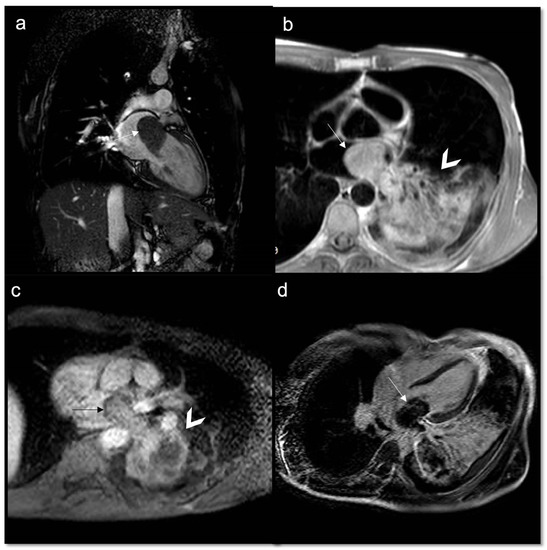

- Malignant masses often show heterogeneous enhancement; typically, angiosarcoma shows early avid enhancement as it is richly vascularized.

| Angiosarcoma | heterogeneous iso | heterogeneous hyper | - | heterogeneous hyper | ++ avid “sunray” aspect | ++ heterogeneous |